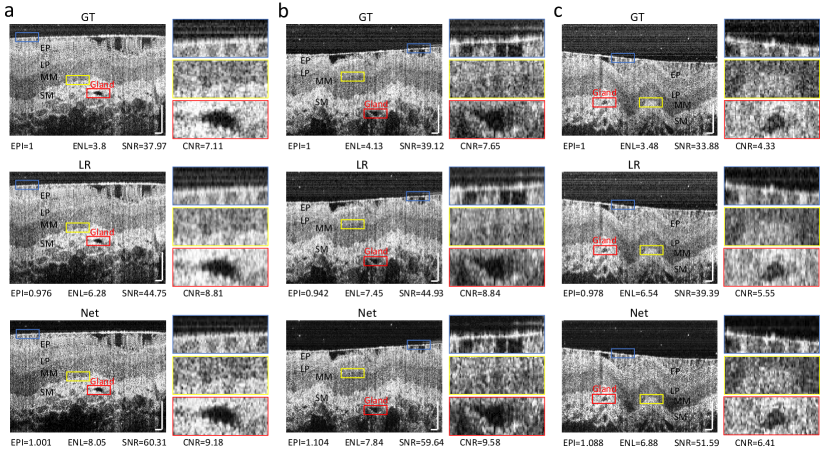

To evaluate the model’s capacity to apply knowledge to various tissues, we perform a test on swine esophagus mucosa OCT images (dataset 5 in Supplementary Table 1), using models𝑚𝑜𝑑𝑒subscript𝑙𝑠model_{s} that is trained on human retinal images. The testing data is acquired from a home-built ultrahigh resolution OCT system. To effectively demonstrate the model’s capability and accuracy in cross-tissue generalization, we utilize the original ultrahigh resolution (2.6 μm𝜇𝑚\mu m) images as GT, and synthesize the low resolution inputs for the model. The brightness of the low resolution inputs is adjusted to 1/3 of the original level to align with the training data. Results from three examples are presented in Fig. 10. The zoomed-in figures in the red and yellow boxes clearly show that the resolution and layer clarity of ‘Net’ images are both higher than LR images. In terms of speckle structure, the speckle pattern and size of ‘Net’ images are more similar to GT compared to LR images. Additionally, the speckle size of ‘Net’ images is finer than that of LR images, which is closely related to the spatial resolution [10]. In terms of layer clarity, the boundaries between MM and SM, LP and MM zoomed in red boxes of ‘Net’ images are clearer than those of the LR images. Specifically, the clarity of the boundaries of the glands shown in yellow boxes within the submucosa layers in the ‘Net’ images has significantly improved compared to the LR images. In terms of quantifying assessment, for EPI, GT images are used as a reference and compared to LR and ‘Net’ images. We can observe that the EPI of LR images are all smaller than 1, which aligns with our observation that tissue surfaces of LR images are blurrier than GT images. Conversely, the EPI of ‘Net’ images are all greater than 1, which also aligns with our observation that the sharpness of the tissue surfaces in the ‘Net’ images is very similar to the GT images. Additionally, the background of the ‘Net’ images is much cleaner than the GT, both of which contribute to the higher EPI values. For ENL, ‘Net’ images have the largest values resulting from the very smoothness of the free space region, i.e. the background. For both SNR and CNR, ‘Net’ images achieve the best performance due to the effective suppression of the background noise. Along with ENL, this can be attributed to the powerful FS prior. It is also worth noting that the blurry effect experienced by LR images leads to better performance on ENL, SNR and CNR due to the smaller standard deviation of the background.

Refer to caption

Fig. 10: Generalization results of swine esophagus mucosa. Ground Truth (GT): Ultrahigh-resolution images feature an axial resolution of 2.3 μm𝜇𝑚\mu m. Low-resolution images (LR) are obtained by convolving the GT with a PSF shown in Supplementary Fig. 2a. Reconstructed high-resolution images (Net) are generated by the network using LR as inputs. The blue boxes indicate the ROI for EPI calculation. EPI of LR and Net is calculated relative to the GT. ENL is computed from the FS region above the tissue surface, which is also used as the background for SNR and CNR calculation. The entire region below the tissue surface is selected as the ROI for SNR and CNR calculation. Yellow boxes delineate the boundaries of different layers, while red boxes indicate areas of low-signal glands within the submucosal layer. EP: Epithelium, LP: Lamina Propria, MM: Muscular Mucosa, SM: Submucosa. All scale bars: 100 μm𝜇𝑚\mu m.